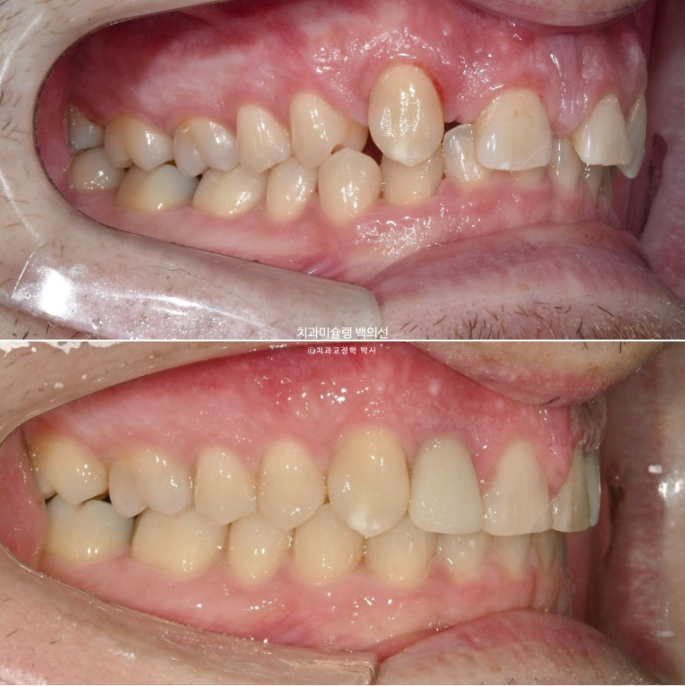

이제 전 후 비교 보겠습니다.

치료기간은 1년 9개월, 재발된 앞니 치축을 바로 잡는데는 4개월이 걸렸습니다.

23.01~25.09

중심선은 잘 맞고 과개교합은 깔끔하게 개선이 되었습니다.

어금니 교합은 물샐틈 없이 좋고 1급 교합관계를 보입니다.

깔끔해진 미소

입매는 잘 유지가 되었습니다.